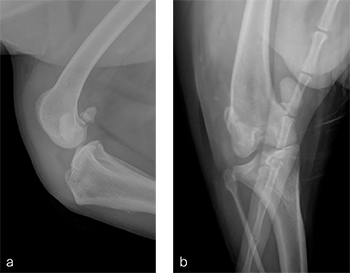

A 1-year- and 6-month-old spayed female Appenzell Cattle Dog weighing 29 kg presented for second opinion after two previous surgical procedures to address a traumatically induced medial patellar luxation. Fig 8 illustrates the initial surgery performed at 1 year and 6 months of age. The patellar luxation was treated with a lateral imbrication. No primary orthopedic procedures were performed. X-rays were obtained 6 weeks postoperatively, and document persistence of the medial patellar luxation. Fig 9 addresses the revision surgery performed to address persistent patellar luxation. A tibial tuberosity transposition was performed to realign the insertion of the patellar tendon without addressing femoral deformity. X-rays were obtained 2 months postoperatively. The patellar luxation persists despite transposition of the tibial tuberosity. Orthopedic examination and preoperative x-rays revealed a grade 3/4 medial patellar luxation (Fig 9). Femoral varus was documented (aLDFA 104; normal 9296) by CT scan (Fig 10). The planned correction was a 10 lateral closing wedge ostectomy, with concurrent sulcoplasty.